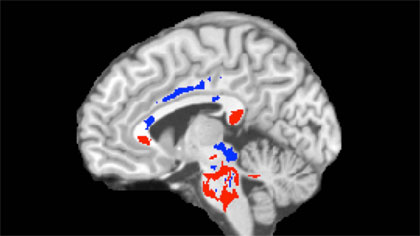

Imaging Technique Helps Predict Long-Term Effects of Concussion

Diffusion tensor imaging (DTI) may be useful in determining early biomarkers of mild traumatic brain injury (mTBI) that relate to patient outcomes one year following injury. DTI may also lead to a better understanding of the brain's mechanisms for repairing or compensating for concussion injuries—information that could speed the development of therapies.